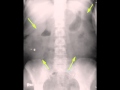

Kidney cancer On X Ray

Kidney, ureter, and bladder xray johns hopkins medication. Study a kidney, ureter, and bladder xray along with motives for the procedure, possible risks, and what to anticipate before, all through and after. Kidney most cancers signs and symptoms, analysis, and treatment. Covers remedy options, followup care, and sources of help for someone lately identified with kidney most cancers. Kidney cancer reasons, signs, remedy, and prognosis. Kidney, or renal, cancer refers to any type of cancer that starts offevolved within the kidney. Discover about the causes, signs, remedy, and outlook. Kidney cancer webcrawler. Kidney cancer is a ailment related to the bizarre and out of control boom of cells in the kidneys, a pair of organs that eliminates waste products from the bloodstream.

Kidney most cancers prognosis cancer. Learn about a kidney, ureter, and bladder xray consisting of motives for the procedure, feasible risks, and what to expect earlier than, at some point of and after. Kidney cancer signs and symptoms and causes mayo health facility. Study kidney cancer (renal mobile most cancers) symptoms and signs, such as include blood inside the urine, pain, fever and weight reduction. Examine approximately kidney most cancers survival. Kidney cancer prognosis cancer. Cancer offers timely, comprehensive, oncologistapproved records from the yank society of clinical oncology (asco), with support from the triumph over cancer. Search a couple of engines for kidney cancer. Kidney most cancers records cancercenter. Cancercenter has been visited by way of 10k+ users within the past month. Kidney most cancers prognosis, symptoms, treatment,. Kidney cancer is a sickness concerning the ordinary and uncontrolled growth of cells in the kidneys, a couple of organs that eliminates waste products from the bloodstream. Kidney cancer data cancercenter. Most cancers presents timely, comprehensive, oncologistapproved information from the yank society of clinical oncology (asco), with aid from the conquer cancer. Symptoms of kidney most cancers canadian cancer society. Signs of kidney most cancers consist of blood in the urine and ache inside the back and facet of the abdomen. Learn about the symptoms of kidney most cancers.